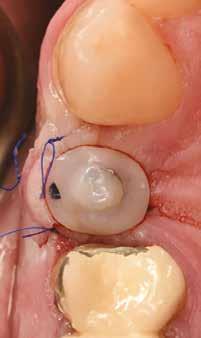

1. ábra: Műtét előtti fogászati panorámafelvétel, amelyen a hiányzó felső állcsont jobb első premolárisát és a szabad véggel rendelkező hidat láthatjuk. — 2. ábra: Az implantátum méreteinek megtervezése CBCT-vel. 3. ábra: Bukkális lágyrészdefektus. — 4. ábra: A biológiai szélesség értékelése a vertikális lágyszövetvastagság alapján. 5. ábra: Palatinális „tekercslebeny” – Palatal roll flap. — 6. ábra: Bredent medical copaSKY 4x10 implantátumbeültetés. 7. ábra: Szubkresztális implantátumbeültetés a várható biológiai szélességnek megfelelően.

8. ábra: Egyéni ínyformázó titánbázison, tulipán alakú emergenciaprofillal. — 9. a. ábra: A sebzárás okkluzális nézete.

(2. ábra). A lágyszövetek értékelése Seibert szerinti I. osztályú csontdefektust állapított meg (3. ábra), ezért a beavatkozáskor palatinális „tekercslebenyt” preparáltunk (palatal roll flap), és implantációt végeztünk, hogy kompenzálni tudjuk a bukkális lágyszövet-behúzódást. Megmértük a vertikális lágyszövetvastagságot, és úgy terveztük, hogy a szubkresztális implantátum beültetése összhangban legyen a biológiai szélesség kialakulásával a transzgingivális gyógyulási periódus alatt (4. ábra)

Az eljárást helyi érzéstelenítés mellett végeztük (4%-os articaine-hidroklorid 1:100 000 adrenalinnal). Papillakímélő, U alakú palatális bemetszést végeztünk, teljes vastagságú nyálkahártyalebeny preparálás történt, a lebenyt bukkálisan feltekertük (5. ábra). A lebeny bukkálisan feltekert részén de-epitelizációt végeztük el, amellyel kompenzálni tudtuk a bukkális lágyszöveti defektust. Szakaszos előfúrást végeztünk, és a bredent copaSKY 4x10 implantátumot 30 Ncm behajtási nyomatékkal helyeztük be (6. ábra). Az implantátumot 1 mm-re szubkresztálisan helyeztük be, hogy később szélesebb emergenciaprofilt tudjunk kialakítani (7. ábra). Az egyedi ínyformázó úgy készült, hogy kompozitot vittünk fel a titánbázisra, és így formáztuk a lágyszöveteket a transzgingivális gyógyulási fázis során (8. ábra). Az egyéni ínyformázó tulipán formájú, hogy kialakítsa a kívánt emergenciaprofilt. A lágyszövetet feszülésmentesen zártuk #6/0 nem felszívódó, monofil fonallal (Optilene, B. Braun Deutschland; 9. a–b. ábra). Posztoperatív röntgenfelvétel készült, ami alapján az implantátum a szomszédos fogakkal párhuzamos elhelyezést mutatott (10. ábra). Posztoperatív utasításokat adtunk a páciensnek a műtéti terület körüli szájhigiénia fenntartása érdekében. A beavatkozást követő egy héttel a varratokat eltávolítottuk, és a kezelt terület kielégítő gyógyulást mutatott (11. ábra). A 4 hónap utáni késleltetett terhelést a páciens kívánsága szerint terveztük.